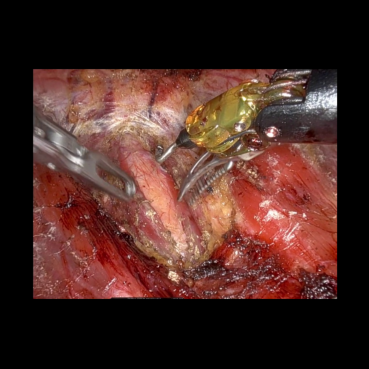

The medical images considered are obtained from a video of a surgery called Bilateral Axillo-Breast Approach (BABA) robotic thyroidectomy, approved by the Research Ethics Committee of Seoul National University Bundang Hospital (B-2504-969-701). This is a thyroid surgery method that is representative of remote access surgery. Clinically, BABA surgery is well known for its superior cosmetic effects and lower complications than conventional thyroidectomy. This surgical method creates surgical incisions in both axillae and both areolas and uses the da Vinci robot to perform the surgery. The surgical video is recorded during the surgery, and the high-resolution images captured are analyzed to develop meaningful clinical studies. Therefore, encoding a high quality of image into a quantum circuit may be significantly important for the future of clinical studies.

We performed similar numerical simulations for more images taken at different frames. Fig. 5 compares the original zero-padded images, the corresponding reconstructed images using FAQPIE with and without the combination of two compression techniques with the same parameter setting as in Fig. 4. A similar observation is made that encoding the images with the two compression techniques results in more efficient FAQPIE with reasonable surgical details and lowered gate counts, as summarized Table 3.

Refer to caption

Figure 5: Comparison of original medical images (left), the corresponding reconstructed images via FAQPIE with no compression technique (middle) and the two compression techniques applied as in Fig. 4 (right).